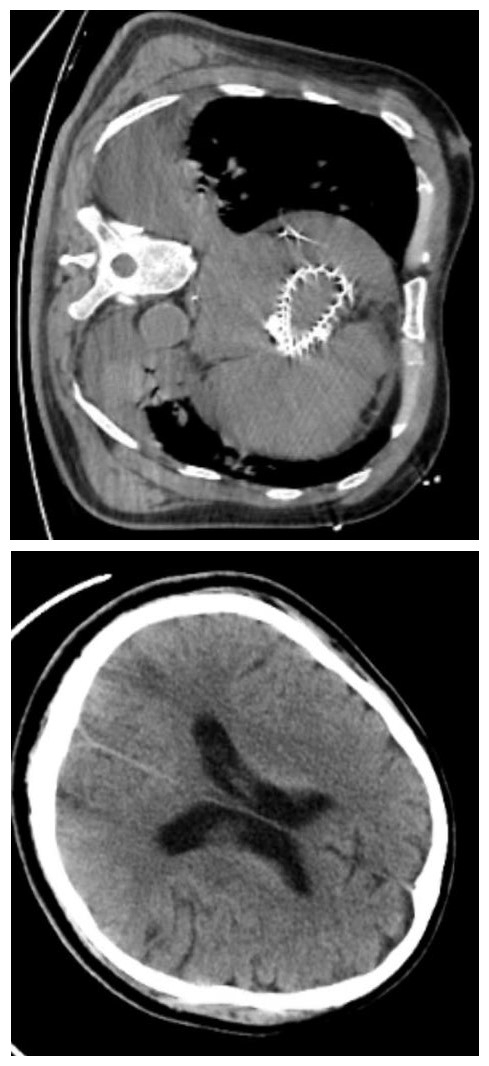

1 资料与方法患者男,78岁,既往有高血压病史10余年,有主动脉瓣狭窄病史,未治疗。2023-10-02 19:00患者无明显诱因下在家中出现呼吸困难,无胸痛,无背痛,21:00患者由120车送至本院抢救中心。来院时患者神志模糊,呼吸急促,SPO2 34%,即予气管插管,21:06患者出现心脏骤停,立即予心肺复苏,21:30启动ECMO团队。22:04 ECMO机器顺利运转。查体:血压82/60 mmHg,心率87次/min,呼吸28次/min,血氧饱和度100%,体温36.3℃。经口气管插管接呼吸机,ECMO转速3 100 r/min,流量3.1 L/min。左侧瞳孔直径1.0 mm,对光反射消失,右侧瞳孔直径1.0 mm,对光反射消失,心音微弱,心律齐,两肺呼吸音清,未闻及干湿性啰音,腹平软,压痛、反跳痛无法配合,肝脾肋下未及,双下肢无浮肿。双下肢ECMO管路留置在位。抢救室辅助检查结果如下:2023-10-02血常规+CRP:WBC 17.5×109/L,Hb175 g/L,PLT 204×109/L,CRP 4.99 mg/L。血生化未见明显异常。cTnT 0.031 μg/L,D二聚体824 ng/mL,BNP 3355.8 pg/mL。血气分析:pH 6.788,PCO2 67 mmHg(1 mmHg=0.133 kPa),PO2 59.8 mmHg,钾3.7 mmol/L,钠136.0 mmol/L,乳酸16.0 mmol/L。肌钙蛋白T 0.031 μg/L,床边心超:左室肥厚,左房增大,主动脉瓣钙化合并重度狭窄(最大开放面积约0.31 cm2),心包少量积液。心电图:加速的室性逸博心律,ST-T改变(V1-V4导联ST段呈水平抬高,I、V5、V6导联ST段呈水平型、下斜型压低0.05~0.5 mV)。当天患者转入ICU。2023-10-07患者出现无尿,予CRRT替代治疗。经院内外专家会诊后考虑患者本次心脏骤停原因为主动脉瓣重度狭窄,故于2023-10-08全麻下行“单根导管的冠脉造影+经导管主动脉瓣置入术(TAVR)”,术中见左主干、左回旋支无狭窄,左前降支中段85%狭窄,远段50%狭窄,主动脉瓣重度狭窄,置入启明26(瓣口)×50(支架长度)mm自膨式瓣膜输送系统,手术过程顺利。术后复查心超,EF45%,10.9撤离ECMO。完善CT(见图 1、图 2)。2023-10-12予气管切开。术后患者出现少量瓣周漏,同时存在胆囊炎、肺部感染、链球菌性败血症、贫血、低蛋白血症、血小板减少症,在补充红细胞、血浆、白蛋白、人免疫球蛋白的基础上,予积极抗感染、抗凝、抗血小板等药物治疗、康复治疗,2023-11-17予停CRRT。2023-11-22予顺利脱机。2023-11-25患者神志由模糊转清醒。2023-12-15患者转入心内科。2023-12-29予局麻下行“药物洗脱冠状动脉支架置入术(PCI)”,术中所见同前,手术过程顺利。术后患者生命体征稳定,后转至康复病房行康复治疗。2024-01-30患者康复出院。

| 图 2 10月26日患者治疗后复查肺部及头颅CT |